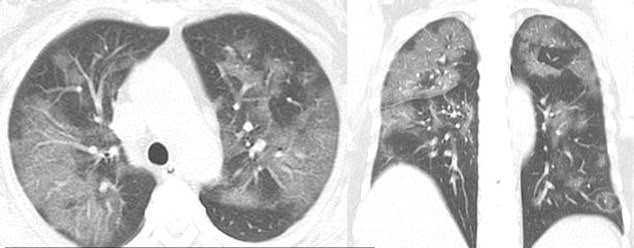

CT scans of a 54-year-old woman who got infected after visiting Wuhan also show the ground glass opacity or partial filling of air spaces.

After suffering from a cough, fever, chest congestion and fatigue for a week, she was diagnosed with severe pneumonia caused by coronavirus.